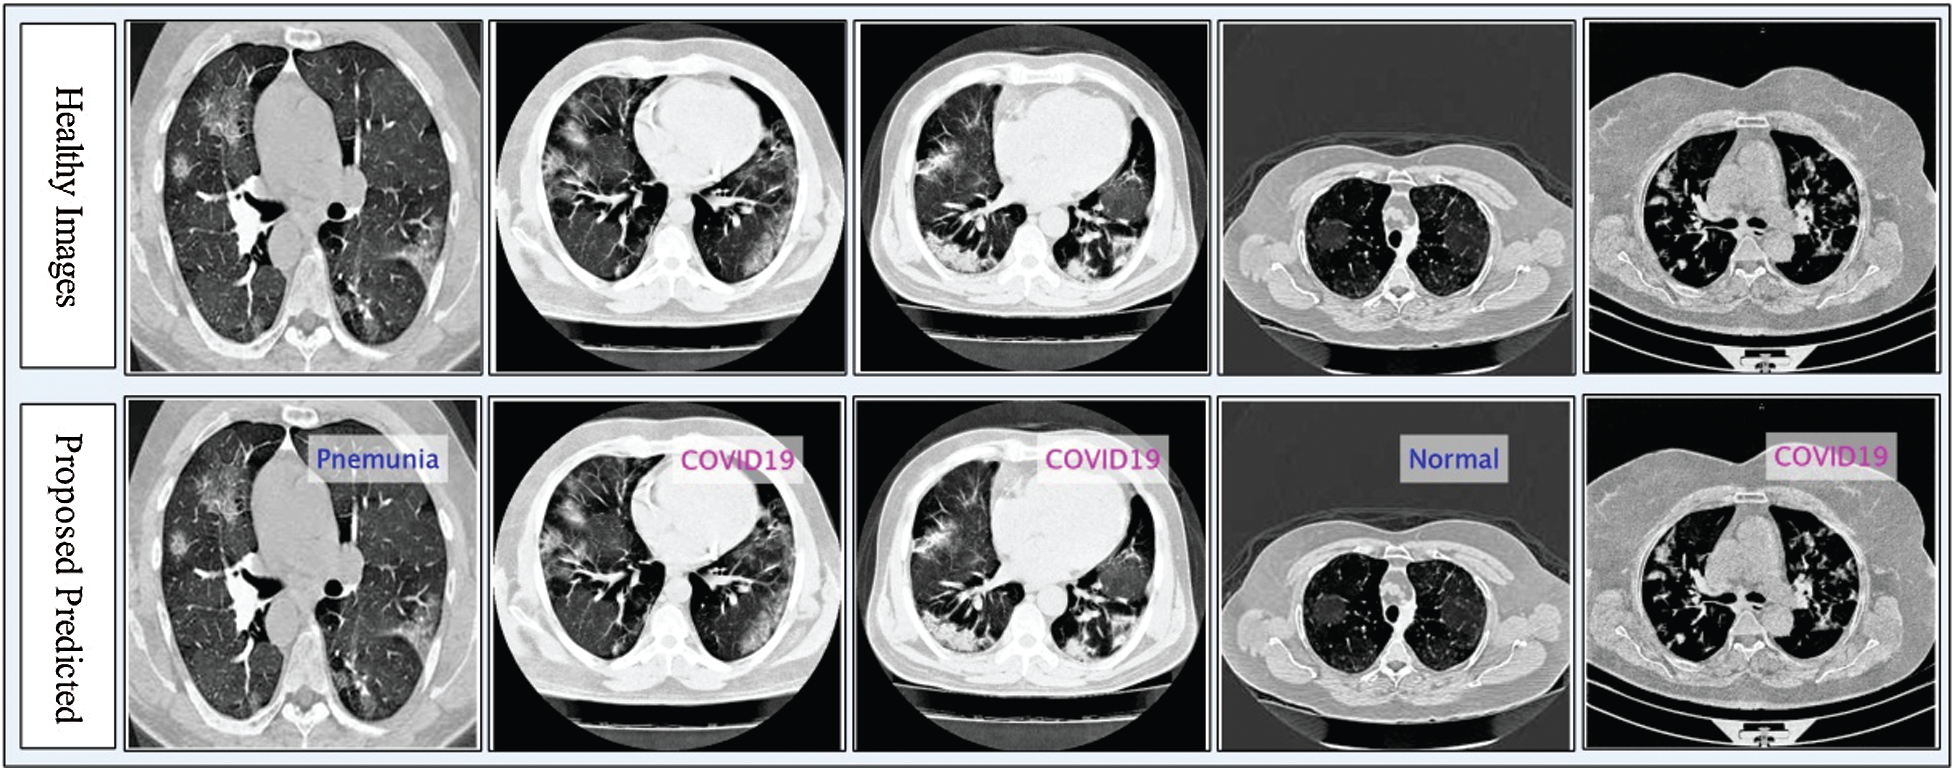

Figure 5: Proposed prediction results in terms of labeled data

The numerical results with accompanying evidence are presented in this section. The results were computed for each step. Tab. 1 presents the classification results after applying a hybrid optimization algorithm on fine-tuned ResNet50 model features. The results shown in this table were calculated for several classifiers using the selected performance measures. The greatest accuracy of this experiment was 92.7% for the ELM classifier. The computed accuracies for the remaining classifiers, i.e., Fine Tree to Softmax, were 86.2%, 84.7%, 83.2%, 90.8%, 90.7%, 91.2%, 91.4%, and 92.1%, respectively. These results indicated that the ELM classifier had the best performance. A number of other measures were also computed to support the performance of ELM; ELM showed sensitivity of 92.67%, precision of 93%, F1-Score of 92.83%, and FNR of 7.33%. To verify the sensitivity of ELM, a confusion matrix was added as shown in Fig. 6. This figure shows that the COVID-19 class correct prediction rate was 94%, and the correct prediction rates for Pneumonia and Normal classes were 96% and 88%, respectively. Thus, the prediction accuracy was best for the Pneumonia class followed by the COVID-19 class. The best time for this experiment was 25.706 s, which was noted during the testing process of all 50% of images, indicating that the hybrid optimization algorithm minimized computational time in real-time testing.

Tab. 2 presents the classification results after applying the hybrid optimization algorithm on fine-tuned DarkNet53 model features. The results shown in this table were calculated for several classifiers using selected performance measures. The ELM classifier showed the highest accuracy of 92.40% in this experiment, which was 0.3% lower than in the experiment shown in Tab. 1. The computed accuracies for the remaining classifiers, i.e., Fine Tree to Softmax, were 87.4%, 88.2%, 90.2%, 90.6%, 91.0%, 90.4%, 91.9%, and 91.6%, respectively. These results indicated that the ELM classifier had the best performance, and that the performance in this experiment was better than that in Tab. 1. A number of other measures were also computed to support the performance of ELM; ELM showed sensitivity of 92.40%, precision of 92.7%, F1-Score of 92.55%, and FNR of 7.66%. To verify the sensitivity of ELM, a confusion matrix was added as shown in Fig. 7. The time was also noted, and the best time for this experiment was 23.927 s showing that the accuracy of the ELM classifier using a hybrid optimized approach for DarkNet features executed faster than ResNet50 features. The performance of optimized DarkNet53 features was also better in comparison to Tab. 1.

The optimal features of both models were fused using the proposed PMDNR approach, and the results are presented in Tab. 3. The results shown in this table indicated that the highest accuracy achieved was 95.6% for the ELM classifier. The other measures were sensitivity of 95.33%, precision of 95.67%, F1-Score of 95.50%, and FNR of 4.67%. The noted computational time of ELM was 20.003 s, which was less than in Tabs. 1 and 2. In addition, the accuracy of ELM after fusion was improved compared to Tabs. 1 and 2. Fig. 8 shows a confusion matrix, which can be used to verify the sensitivity of ELM. As shown in this figure, the correct prediction rates for Pneumonia and COVID-19 images were 99% and 96%, respectively, representing significant improvements compared to Figs. 6 and 7.